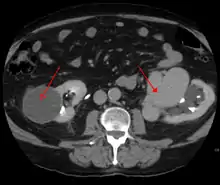

AVMs are diagnosed primarily by the following imaging methods:[12]

- Computerized tomography (CT) scan is a noninvasive X-ray to view the anatomical structures within the brain to detect blood in or around the brain. A newer technology called CT angiography involves the injection of contrast into the blood stream to view the arteries of the brain. This type of test provides the best pictures of blood vessels through angiography and soft tissues through CT.